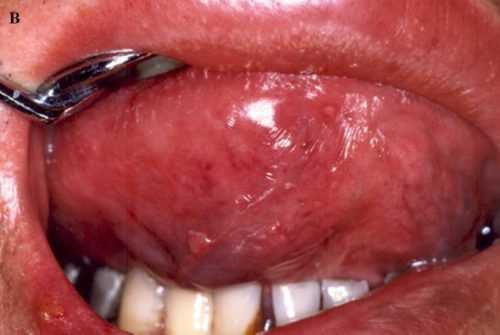

ΠΠΠ§

ΠΠΠ§Π£ Π±ΠΎΠ»ΡΠ½ΡΡ , ΡΡΡΠ°Π΄Π°ΡΡΠΈΡ Π²ΠΈΡΡΡΠΎΠΌ ΠΈΠΌΠΌΡΠ½ΠΎΠ΄Π΅ΡΠΈΡΠΈΡΠ°, Π½Π΅ΡΠ΅Π΄ΠΊΠΎ Π²ΡΡΡΠ΅ΡΠ°Π΅ΡΡΡ Π³ΡΠΈΠ±ΠΊΠΎΠ²Π°Ρ ΡΠΎΡΠΌΠ° ΡΡΠΎΠΌΠ°ΡΠΈΡΠ° (ΠΌΠΎΠ»ΠΎΡΠ½ΠΈΡΠ°) Ρ Ρ Π°ΡΠ°ΠΊΡΠ΅ΡΠ½ΡΠΌΠΈ ΡΠΈΠΌΠΏΡΠΎΠΌΠ°ΠΌΠΈ.

Π ΡΠ°ΠΊΠΆΠ΅ Π² ΡΠΎΡΠΎΠ²ΠΎΠΉ ΠΏΠΎΠ»ΠΎΡΡΠΈ ΠΎΠ±ΡΠ°Π·ΡΡΡΡΡ Π³Π΅ΡΠΏΠ΅ΡΠΈΡΠ΅ΡΠΊΠΈΠ΅ Π²ΡΡΡΠΏΠ°Π½ΠΈΡ Π² Π²ΠΈΠ΄Π΅ Π²ΠΎΠ»Π΄ΡΡΠ΅ΠΉ, ΠΏΡΠ΅Π²ΡΠ°ΡΠ°ΡΡΠΈΡ ΡΡ Π² Π±ΠΎΠ»Π΅Π·Π½Π΅Π½Π½ΡΠ΅ ΡΠ·Π²Ρ.

Π¦ΠΈΡΠΎΠΌΠ΅Π³Π°Π»ΠΎΠ²ΠΈΡΡΡΠ½Π°Ρ ΠΈΠ½ΡΠ΅ΠΊΡΠΈΡ Π²ΡΠ·ΡΠ²Π°Π΅Ρ ΠΏΠΎΡΠ²Π»Π΅Π½ΠΈΠ΅ Π½Π΅ΠΊΡΠΎΡΠΈΡΠ΅ΡΠΊΠΈΡ ΡΠ·Π² Π½Π° Π΄Π΅ΡΠ½Π°Ρ ΠΈΠ»ΠΈ ΡΠ·ΡΠΊΠ΅.

ΠΠ±ΡΠ°ΡΠΈΡΠ΅ Π²Π½ΠΈΠΌΠ°Π½ΠΈΠ΅! ΠΠ·-Π·Π° ΠΎΡΡΡΡΡΡΠ²ΠΈΡ ΠΈΠΌΠΌΡΠ½Π½ΠΎΠΉ Π·Π°ΡΠΈΡΡ Ρ ΠΠΠ§-ΠΈΠ½ΡΠΈΡΠΈΡΠΎΠ²Π°Π½Π½ΡΡ ΠΏΠ°ΡΠΈΠ΅Π½ΡΠΎΠ² ΠΎΠ±ΡΡΠ½ΡΠΉ ΡΡΠΎΠΌΠ°ΡΠΈΡ ΠΏΡΠΎΡΠ΅ΠΊΠ°Π΅Ρ Π² ΡΡΠΆΠ΅Π»ΠΎΠΉ ΡΠΎΡΠΌΠ΅, ΡΡΡΠ΄Π½ΠΎ ΠΏΠΎΠ΄Π΄Π°Π΅ΡΡΡ Π»Π΅ΡΠ΅Π½ΠΈΡ, Π²ΡΠ·ΡΠ²Π°Π΅Ρ ΠΎΡΠ»ΠΎΠΆΠ½Π΅Π½ΠΈΡ, ΡΠΎΠΏΡΠΎΠ²ΠΎΠΆΠ΄Π°Π΅ΡΡΡ ΠΏΡΠΈΡΠΎΠ΅Π΄ΠΈΠ½Π΅Π½ΠΈΠ΅ΠΌ Π²ΡΠΎΡΠΈΡΠ½ΠΎΠΉ Π±Π°ΠΊΡΠ΅ΡΠΈΠ°Π»ΡΠ½ΠΎΠΉ ΠΈΠ½ΡΠ΅ΠΊΡΠΈΠΈ.